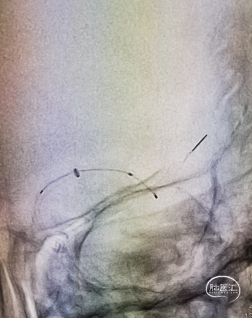

构建治疗通路,微导管穿过闭塞段后造影确认真腔,置入Syphonet®取栓支架,支架通体显影,提供良好的视觉反馈,全程可视化操作。

首过效应阳性。

沿取栓支架的输送导丝送入SacSpeed®球囊扩张导管,将球囊置于狭窄段充盈球囊进行扩张。